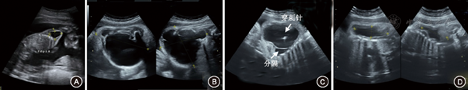

经超声科、优生优育科、产科、儿内科、儿外科会诊,因胎儿巨大团块位于右侧胸壁与上肢之间,且张力大致胎儿右上肢始终呈外展状态,胎儿有可能出现肩难产,决定在超声引导下行宫内胎儿囊性团块穿刺抽液术。孕38周+4胎儿右侧腋下胸壁囊性团块大小为101 mm×110 mm×95 mm,在超声引导下穿刺针刺入该团块腔内(图1C),抽出淡黄色清亮液体400 ml,实验室检查证实为淋巴液(淋巴细胞比例大于85%),见表1;术后团块缩小为62 mm×51 mm×21 mm(图1D)。再将博来霉素1 mg(瀚晖制药有限公司,1.5万单位博来霉素溶解于生理盐水5 ml)在超声引导下注入囊性团块内,每个分隔内都注入博来霉素进行硬化治疗。抽吸术后第2天,孕妇经阴道分娩一女活婴,1和5 min Apgar评分均为10分,右侧腋下胸壁情况见图2A;超声检查显示婴儿囊性团块大小57 mm×47 mm×38 mm(因当时为床边B超,未存图片)。生后42 d复诊,在超声引导下将博来霉素2.5 mg(用生理盐水5 ml溶解)注入囊性团块内。随访10个月时,婴儿状况良好(图2B),MRI检查未见明显囊性团块(图3A)。随访30个月时,超声复查仅皮下软组织增厚,内无液性暗区(图3B),左侧腋下胸壁软组织正常(图3C)。